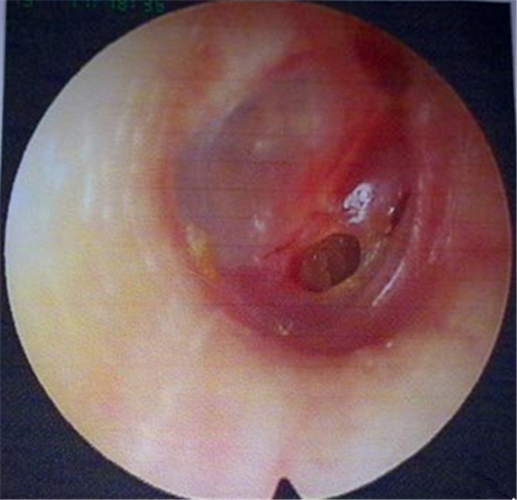

中耳炎鼓膜穿孔

中耳炎使鼓膜穿孔